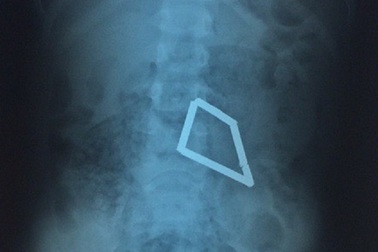

Bé trai bị thủng ruột vì 8 thanh nam châm xếp hình trong bụngNhập viện trong tình trạng đau bụng nhiều ngày không rõ nguyên nhân, bệnh nhi được bác sĩ phát hiện trong ổ bụng có nhiều dị vật xếp thành hình thang vuông. Các bác sĩ đã thực hiện phẫu thuật nội soi lấy ra 8 thanh nam châm hút chặt vào nhau gây thủng ruột bệnh nhi.